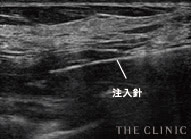

アクアフィリング豊胸やアクアリフト豊胸のしこりは、触診だけの曖昧な見当で取り除けるものではありません。海外では「暗闇での手術」と危険視される行為です。

THE CLINIC ではアクアフィリング豊胸やアクアリフト豊胸後のしこりを確実に溶解・除去するため、必ず乳腺用エコーを使用。最短ルートでしこりを取り除けるので、体への負担を最小限に抑えます。

その点、THE CLINIC では全院にデジタル乳腺用エコー「エラストグラフィ」を導入。施術前に必ずエコー検査を行い、細かい情報を把握した後、適切な治療方針を決定します。

術後のエコー確認で安心を提供

バスト内は実際に見ることができないので、手術でアクアフィリングやアクアリフトが本当に溶解・除去されたのか不安に思われる方も多いはず。そんな方には麻酔から目が覚めた後、乳腺用エコーを使って胸の様子を確認していただくことが可能です。しこり等が完全に除去されていることを、その目でお確かめください。